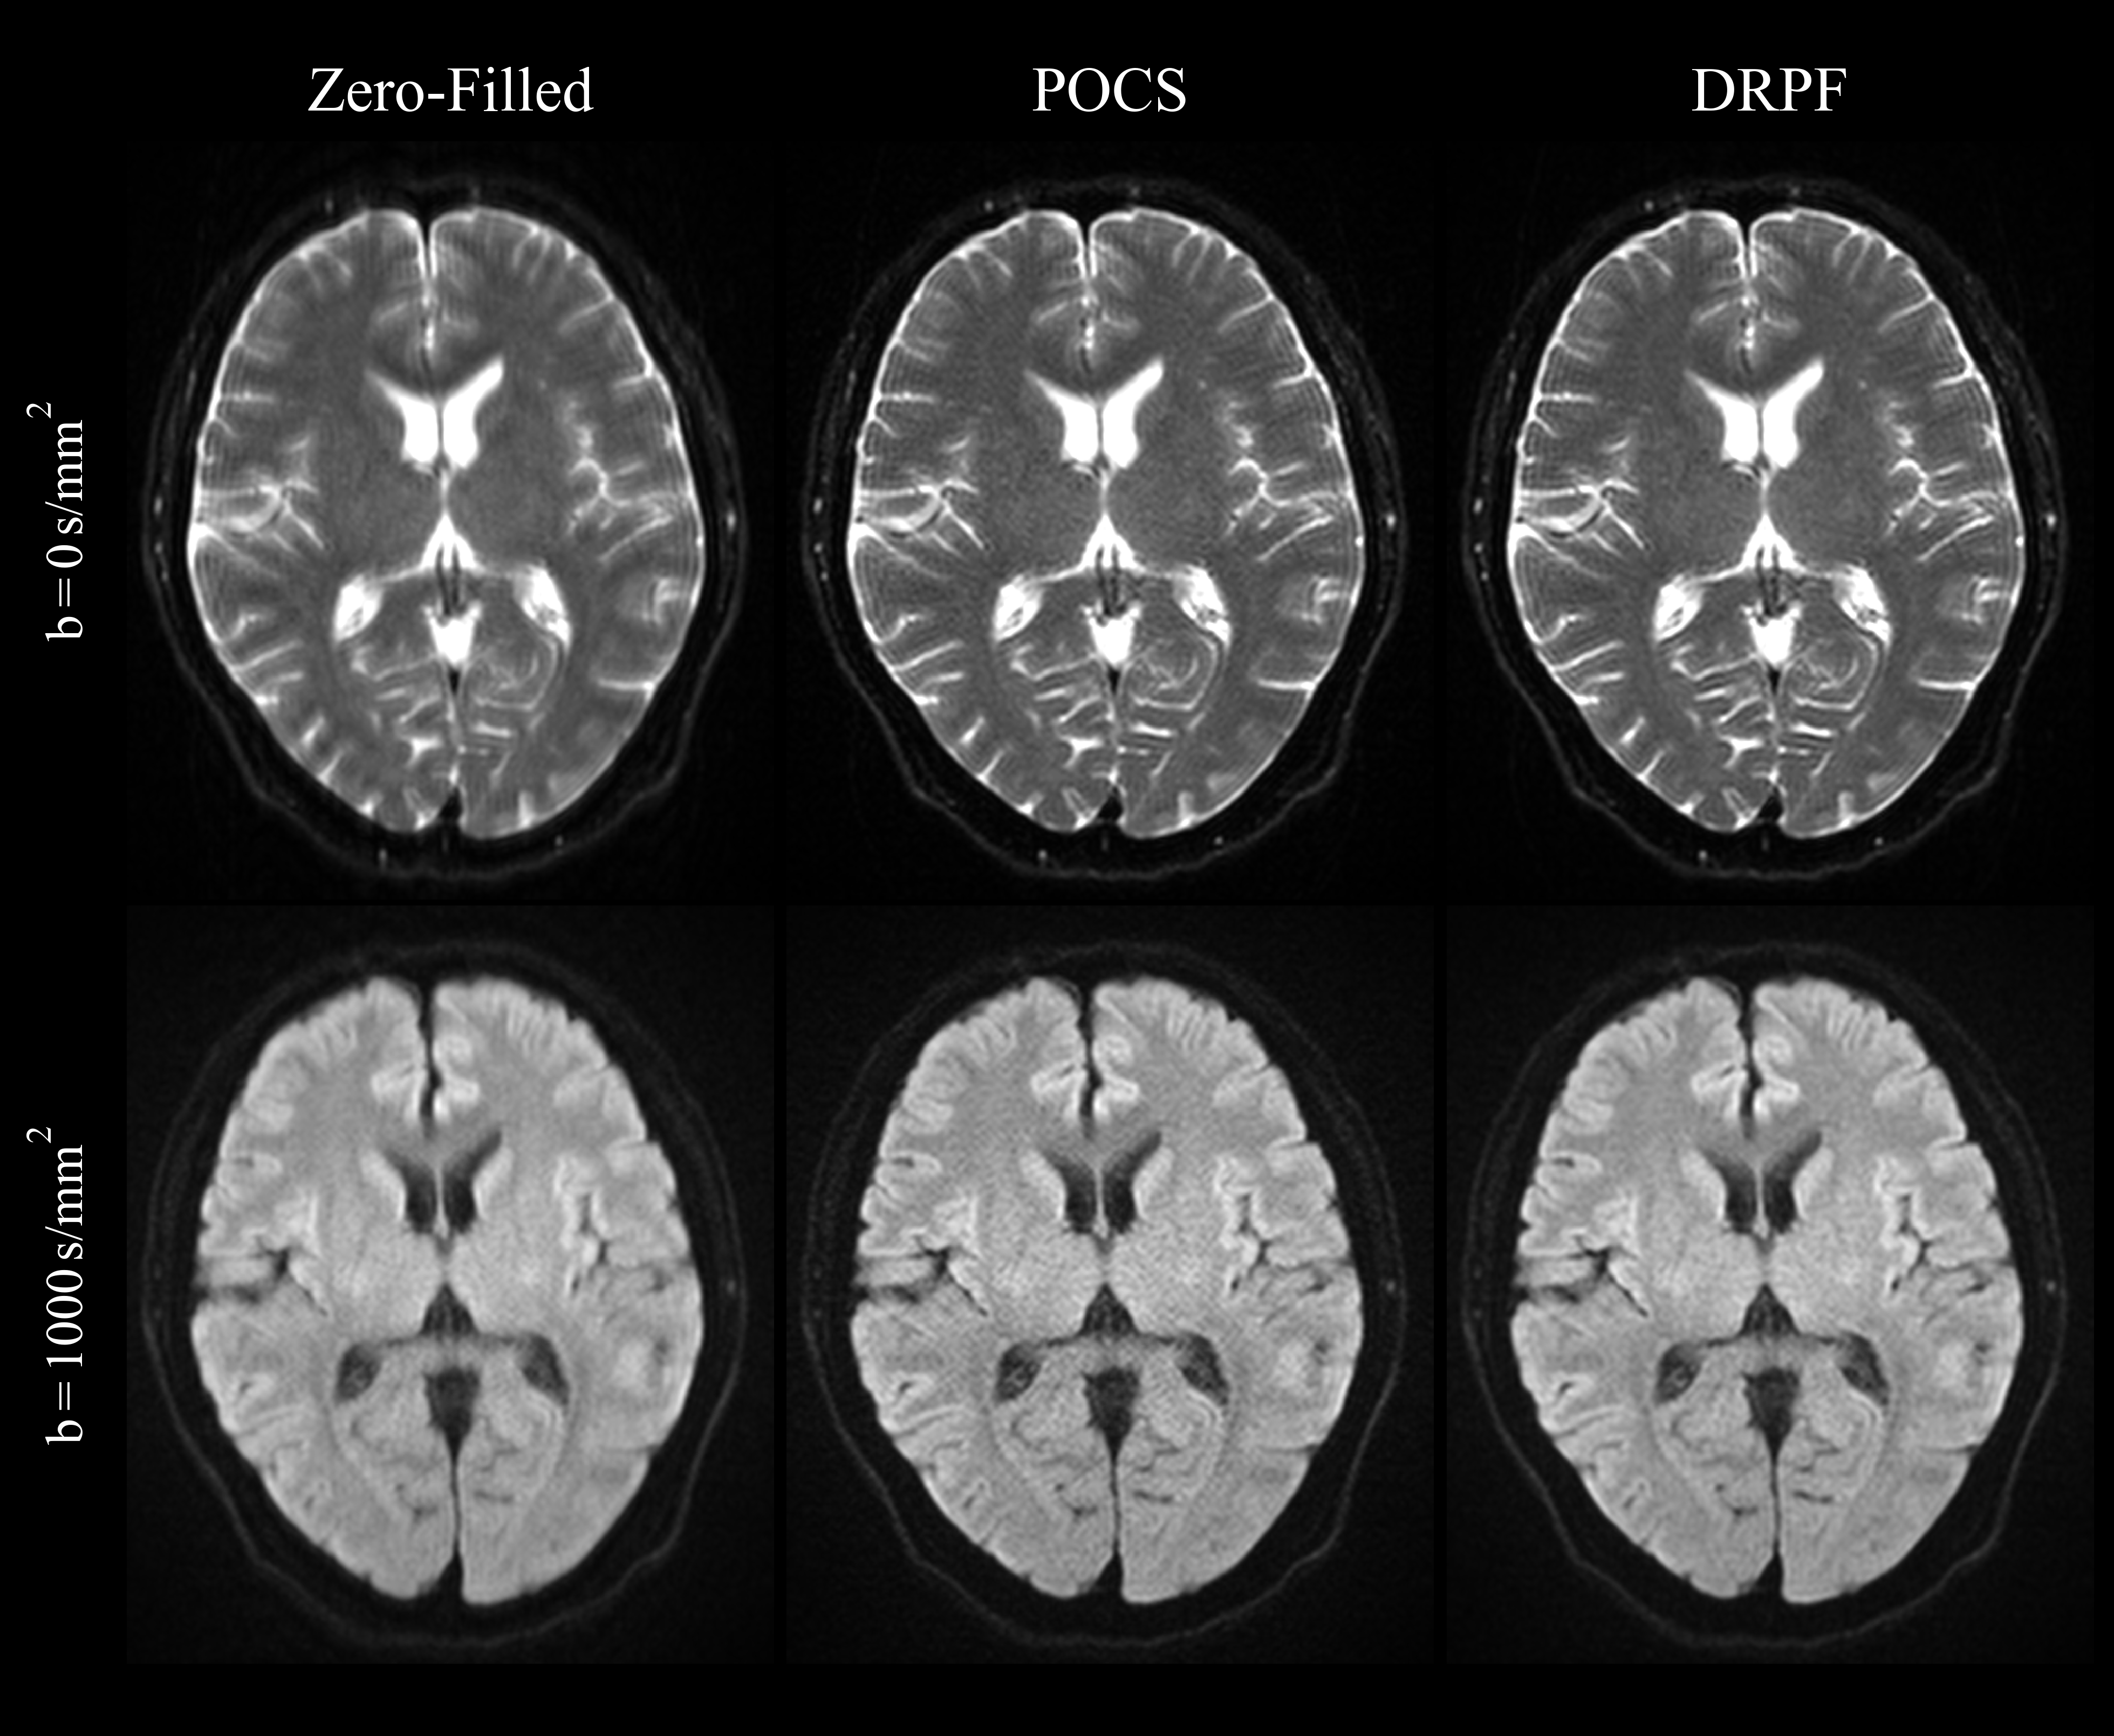

Results on prospectively sub-sampled brain data are presented in Figure 7. Both POCS and DRPF alleviate blurring introduced by zero-filling effectively. However, POCS leads to noise amplification which becomes more profound for the higher b𝑏b-value. Since phase variations are comparatively moderate in brain DWI, severe artifacts such as signal voids cannot be observed. Although being trained exclusively on liver data, DRPF is able to reconstruct brain images which feature sharp edges at tissue boundaries but at the same time appear more homogeneous in iso-intense regions compared to POCS.

Refer to caption

Figure 7: Qualitative evaluation of zero-filling, POCS and DRPF on a representative brain slice (PFF=5/8PFF58\text{PFF}=5/8, 3 T) acquired without (b=0𝑏0b=0 s/mm2, top row) and with (b=1000𝑏1000b=1000 s/mm2, bottom row) diffusion weighting.